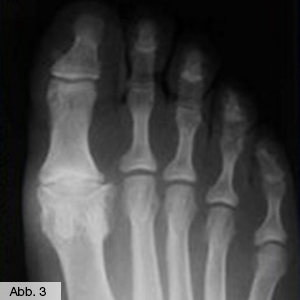

Arthrose des Zehengelenks

Wie auch bei den großen Gelenken führt der Verschleiß des Großzehengrundgelenks (Abb. 3) zu Bewegungs- und Belastungsschmerzen. Da dieses Gelenk für einen normalen Abrollvorgang beim Gehen äußerst wichtig ist, kann eine Arthrose sehr behindernd sein. Wenn eine Ruhigstellung des Gelenks durch Einlagen nicht mehr ausreicht, können hier operative Eingriffe helfen. Die Behandlungsspanne reicht von dem einfachen Abtragen störender Knochenzacken (Cheilektomie) über Knorpelplastiken bis zum Einsatz eines künstlichen Großzehengrundgelenks (Abb. 4) oder einer Versteifung.